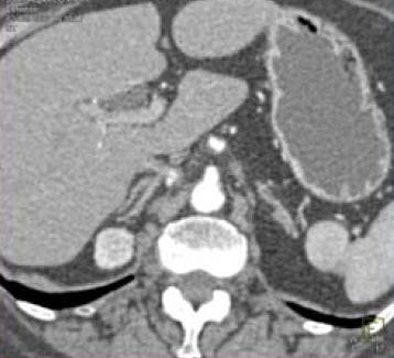

In one patient example, a small hypervascular lesion in the left kidney could not be seen in the early corticomedullary phase, even when the image was viewed in multiple planes, in volume rendering (VR) and maximum-intensity projections (MIPs). It became "a fairly obvious lesion on excretory-phase imaging," Fishman said.

![]() |

| Subtle renal cell carcinoma not visualized in any plane in the arterial phase (above) becomes fairly obvious in excretory-phase image (below). All images courtesy of Dr. Elliot Fishman. |